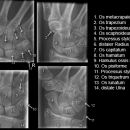

Handgelenk a.p.

Beurteilungskriterien

• Kontinuität der drei Karpalbögen:

Proximaler Bogen: proximale Gelenkflächenkonturen von Scaphoid, Lunatum und Triquetum

Mittlerer Bogen: distale Gelenkflächenkonturen von Sacphoid, Lunatum und Triquetum

Distaler Bogen: proximale Gelenkflächenkonturen von Capitatum und Hamatum

Fehlende Abgrenzbarkeit, Versatz oder Unterbrechung sind als pathologisch zu bewerten und deuten auf eine Luxation hin.

Trapezförmige Darstellung des Lunatum in Neutralstellung? Augenzeichen des Hamulus? Superposition von Pisiforme und Triquetum? Metacarpale III in Projektion innerhalb der Radiusgelenkfläche? Lunatum zu >50% über Radiusgelenkfläche? Cave: bei Radial- oder Ulnarduktion wandert das Lunatum in umgekehrter Richtung.

• Gelenkspaltweiten des Radiocarpalgelenk 2 – 2,5mm, der Carpometacarpalgelenke 1 –2mm, distales Radioulnargelenk 2mm, Gelenksspaltweiten der Intercarpalgelenke 1,5 – 2mm

Cave: SL-Dissoziation (Ruptur des SL- Bandes, häufigste Gefügestörung): Terry-Thomas-Sign = SL-Spalt > 3mm, Siegelringzeichen = Ringförmige Transparenzminderung im mittleren Scaphoiddrittel durch orthograde Projektion der Taille infolge Rotation.